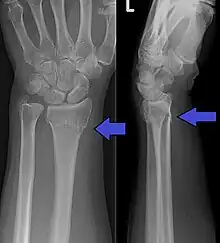

Fracture de Pouteau-Colles

Une fracture de Pouteau-Colles est une rupture osseuse, avec déplacement dorsal, du radius (situé dans l'avant-bras). Elle se caractérise par un déplacement du poignet et donc de la main.

- De face : trait simple, transversal, sus articulaire, métaphysaire.

- Bascule externe de l'épiphyse radiale.

- Horizontalisation de la ligne bi-styloïdienne.

- De profil : bascule postérieure épiphyse radiale.